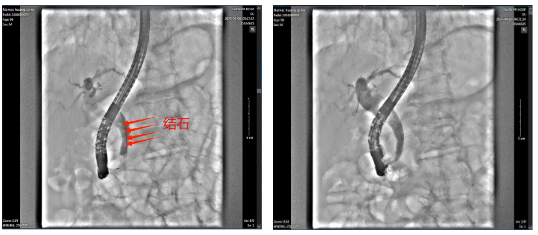

在消化内科一病区、内镜中心、麻醉科、介入室的多学科联合协作下,手术顺利完成,术程不到一个小时,4枚大小约0.3cm×0.4cm-1.0cm×0.5cm褐色结石被完整取出。术后患者恢复快,仅3天便康复出院。

术前胆道镜 术后胆道镜